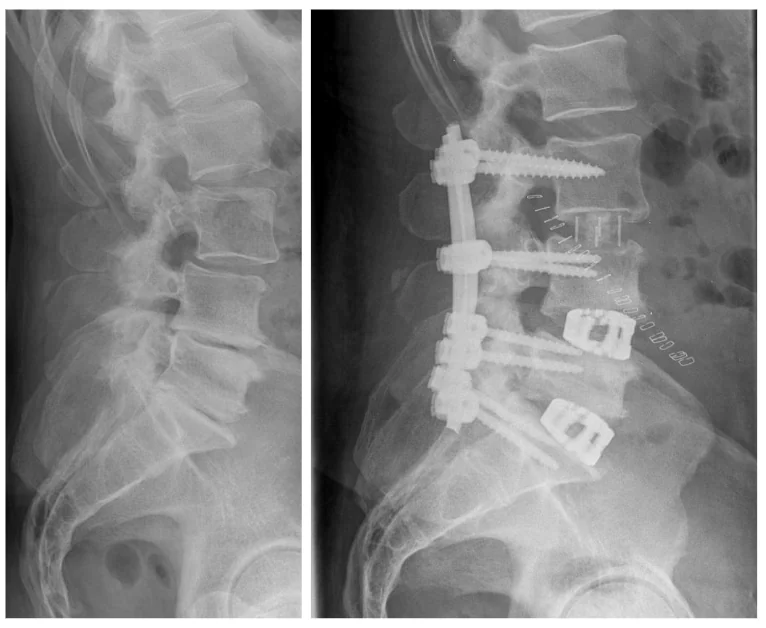

Radiografii din incidența anteroposterioară și laterală ale unui pacient cu spondilolistezis L4-L5 ce a suferit o intervenție chirurgicală de decompresie și fuziune intercorporeala posterioară transforaminala cu șuruburi pediculare și cage PEEK (PLIF)

Radiografii din incidența laterală preoperator si postoperator ale unui pacient cu spondilolistezis L3-L4 si stenoza lombara multietajata ce a suferit o intervenție chirurgicală de decompresie și fuziune intercorporeala anterioara si laterala retroperitoneala cu cage-uri si fixare cu șuruburi pediculare L3-S1. Pe imaginea postoperatorie se observa corecția spondilolistezisului, refacerea lordozei lombare fiziologice, decompresia foraminala indirecta prin creșterea diametrului găurilor de conjugare.